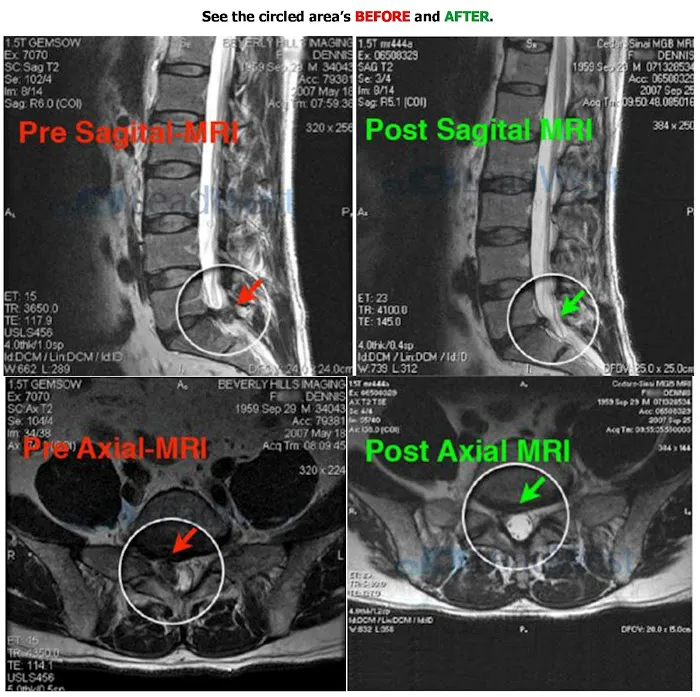

- Spinal Decompression Therapy (DRX9000): Utilizing the state-of-the-art DRX9000 machine, this therapy gently stretches the spine to create negative pressure within the discs. This process helps to reposition herniated or bulging discs, allowing vital nutrients and oxygen to flow back into the disc for healing, and relieving pressure on nerves.

- Proven Track Record with Severe Cases: The testimonials highlight success stories even with significant disc herniations (e.g., 11mm lumbar disc), where other medical professionals suggested surgery. This demonstrates the effectiveness of their therapy even in severe, debilitating situations.

- Rapid and Sustained Pain Relief: Patients often report significant improvement within a few visits or weeks, with dramatic pain reduction (e.g., 90% gone by the 15th visit) and complete elimination of pain within 10 weeks for some. The therapy helps the body heal itself, leading to lasting results.

- Genuine Alternative to Surgery and Injections: The center provides a viable and highly effective alternative for patients who wish to avoid invasive spinal surgery, the risks associated with it, or repeated steroid injections. This offers immense peace of mind and preserves quality of life.

- Comprehensive Consultation Process: Dr. Shannahoff takes the time to listen, review medical imaging (like MRIs), and provide a thorough consultation to ensure that spinal decompression is the appropriate treatment for the patient's specific condition.